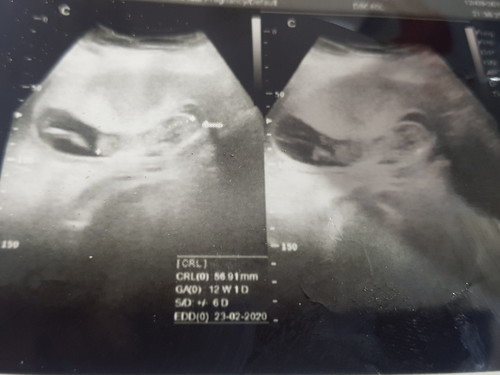

bentuk kantung rahim

Mau tanya apakah normal bentuk kantung rahim posisinya kaya menjepit janin di dlm..tdk pada umumnya liat hasil usg org lain pada bulat2 luas gtu kantung rahimnya